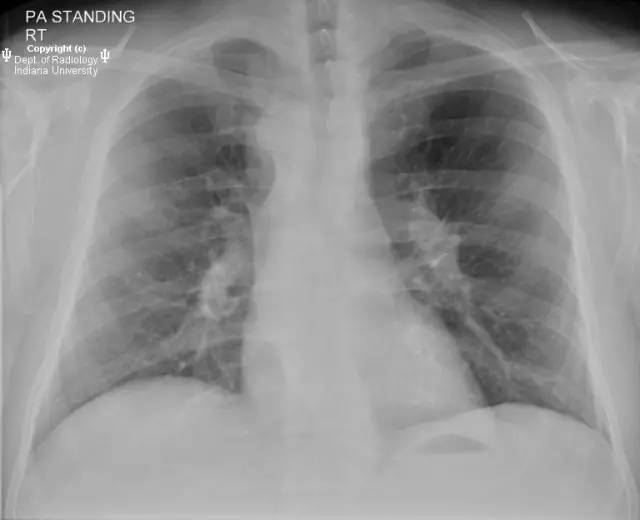

【影像学表现】胸部平片示右位主动脉弓,肺动脉突出,双肺清晰。CT示右位主动脉弓,并右位降主动脉,迷走左锁骨下动脉起自后方,从食管后走形形成血管环。迷走左锁骨下动脉与憩室相关(Kommerell)。食管因左锁骨下动脉及憩室而向前移位。

【诊断】右位主动脉弓并血管环形成、迷走左锁骨下动脉并Kommerell憩室

Right-sided aorticarch, with vascular ring and aberrant left subclavian with Kommerell\’sdiverticulum